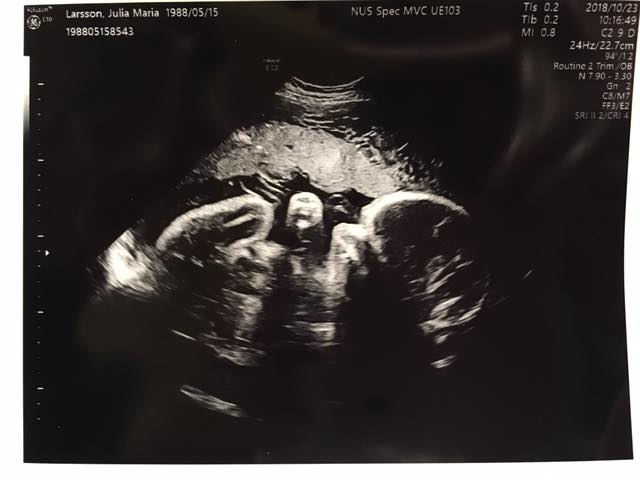

Igår var vi på vårt sista ultraljud (nr 4) och förra veckan avslutades föräldragruppen. Två månader till beräknad ankomst av det kavata lilla livet som växer i min livmoder. Under mitt hjärta, vem är du? Jag är så otroligt nyfiken på vad det är för person som finns där och som snart kommer finnas mitt framför oss. Overkligt, javisst. Men sanningen är att detta är ett fullkomligt verkligt. När ska jag förstå det? Kanske under krystvärkarna eller under sömnlösa nätter när du skriker. När bröstmjölken sprutar eller första gången vi får ögonkontakt? Tiden vägleder.